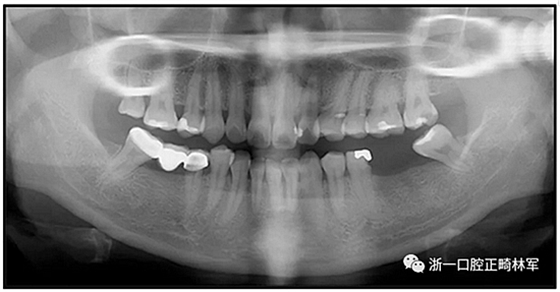

36歲;女性;尋求下頜左后方區(qū)域間隙管理的建議(圖1和圖2),通過治療獲得了良好的牙頜面效果(圖3和圖4)。她被診斷患有骨性I類和代償性牙性II類錯合畸形,并且上頜左側尖牙缺失(圖1和2)。大約七年前,由于不可修復的齲齒,拔除了下頜左側第一和第二磨牙(圖5)。37相鄰的第三磨牙向近中移動并傾斜入間隙,導致無牙頜間隙減小至約14 mm(圖2和圖5)。臨床和影像學評估顯示多發(fā)性齲損和在下頜右側567處有一不良的固定橋修復體(圖1和5)。此外,下頜左中切牙缺失,造成下頜中線向左側偏移約3 mm(圖1和圖2)?;颊咦栽V,她的右上第一前磨牙和左上尖牙在13歲時由其家庭牙醫(yī)拔除,因為它們被阻塞到頰側萌出(圖1)。上頜第二磨牙缺失(未知病因),并且相鄰的第三磨牙已經(jīng)轉移到第二磨牙間隙中。如補充材料所示,美國正畸學差異指數(shù)DI是28分。種植體部位(下頜左側和右側第一磨牙)由于復雜性得到額外4分(補充材料)。

圖5. 治療前的側位片(上圖)和全景(下圖)的X光片

總之,這種復合錯合畸形是一個很嚴重的問題,需要進行認真的多學科序列治療。治療后X光片(圖6)和重疊頭影測量圖(圖7)記錄了跨學科治療結果。